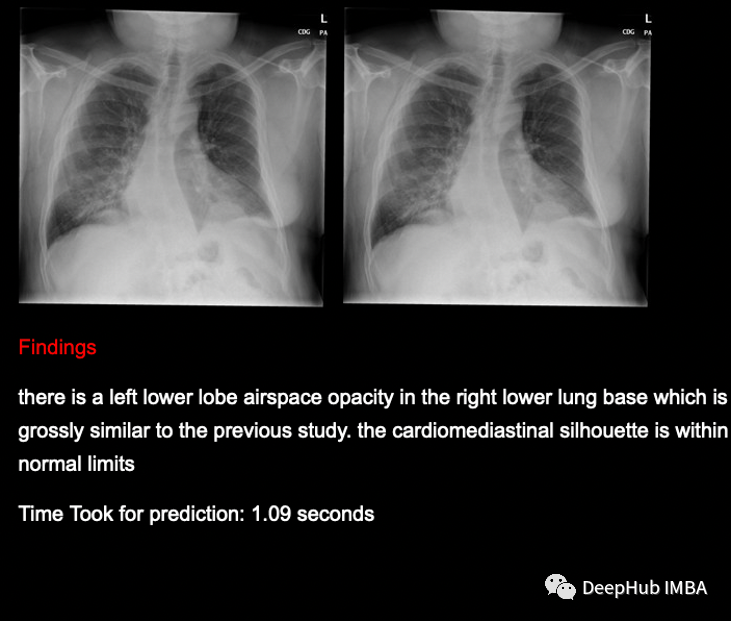

图像描述是生成图像文本描述的过程。它使用自然语言处理和计算机视觉来为图像生成描述的文本字幕。一幅图像可以有很多个不同的描述,但是只要它正确地描述了图像,并且描述涵盖了图像中的大部分信息就可以说是没问题的。下面是示例图片和生成的描述文字。

使用Greedy Search测试标题预测和BLEU评分

为什么只有28.3%的BLEU得分。这时深度学习需要大量的数据,但我们提供给模型的数据非常少,即使在大量重采样之后,也会偏向于非疾病数据,因此这个BLEU评分对于我们使用的数据来说已经很好了,如果我们有大量的数据,那么相同的模型将表现得非常好,并给出更好的结果。

预测是有意义的,模型能够预测疾病和非疾病数据。为了提高模型的性能,我们需要更多的数据,以便我们的模型训练得更好,给出更好的输出。

我们能够成功地为x射线图像生成标题(发现),并能够通过带有GRUs的基于全局注意力的编码器-解码器模型实现约28.3%的BLEU评分。由于我们拥有的数据非常少,而且偏向于非患病数据,我们无法获得非常好的BLEU得分,但如果我们有大量平衡的数据,那么同一段代码可以非常好地预测图像的标题。